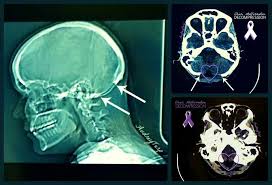

Fractured Vp Shunt Frontal Radiograph Of The Cervical Spine Edge Enhanced Shows A Fracture Of The Ventriculo Peritoneal Shunt Dr Vp Shunt Pet Ct Radiography

Vp shunt skull x ray. Patients may have negative ct findings but positive x ray findings 2. Ensuring clear visualization of the shunt in the skull and its path down the cervical region. 8 views ap and lateral abdomen ap and lateral chest ap and lateral c spine ap and lateral skull.

The programmable csf shunt valve has become an important tool in hydrocephalus treatment particularly in the nph population and in pediatric patients with complex hydrocephalus. The shunt series is a set of radiographic images performed to assess the location and integrity of a ventriculoperitoneal shunt. Usually a simple lateral skull x ray helps to identify the type of valve and it s adjustment.

Shunt series ap lateral skull and chest abdominal x ray as a baseline for future comparison some surgeons obtain these films immediately post op in case some immediate revision is indicated e g. Ventriculoperitoneal vp shunts are a device used to shunt cerebrospinal fluid in the treatment of hydrocephalus. The purpose of this study is to provide a single reference for the identification of programmable shunt valves and the interpretation of programmable shunt valve settings.

A ventriculoperitoneal vp shunt is a medical device that relieves pressure on the brain caused by fluid accumulation. Shunt series for vp shunt x ray guideline. Reviewed 2016 amr.

The verification of shunt adjustment so called opening pressure and also the primary identification of the implanted valve type can be a problem in daily practice. Frontal radiograph of the cervical spine edge enhanced shows a fracture of the ventriculo peritoneal shunt drainage tube black and white arrows with caudal retraction of the distal fragment. If the shunt is somewhat superimposed on.

Ventricular catheter tip in temporal horn. The external portion of the catheter is connected to a valve that regulates the flow of csf based on a preset pressure.